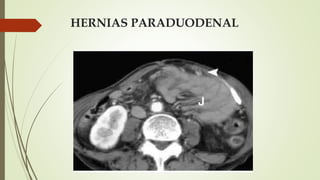

HERNIAS PARADUODENAL.

 Las fosas paraduodenales se originan como anomalías peritoneales

congénitas debido al fracaso de la fusión mesentérica con el peritoneo

parietal y una rotación anormal asociada durante el encarcelamiento del

intestino delgado bajo el colon en desarrollo

HERNIAS PARADUODENAL